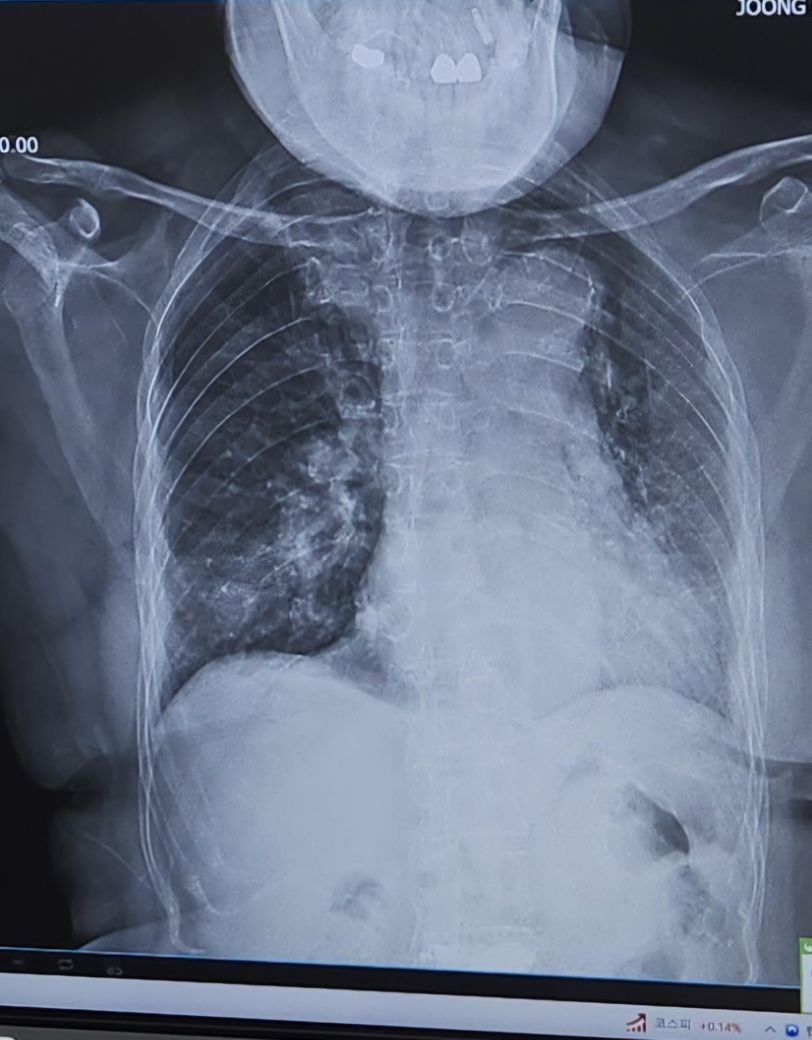

각각 다른 병원에서 찍은 엑스레이 사진인데

위에꺼가 일주일전 아래가 일주일후입니다.

아래는 풀어져서 퍼진것처럼 보여서요.

위에사진의 뭉덩이진것이 아래사진에서 풀어진것이라면. 호전되고있는건지 궁금합니다

• 2번 째 사진

딱히 호전되었다고는 보이지 않습니다.

폐렴의 정확한 상태는 단순히 엑스레이로는 판단 불가합니다

임상적 맥락을 모두 봐야 하기 때문에 혈액검사 결과는 물론 증상의 호전도까지 모두 총체적으로 평가해야 가능합니다

담당 의사와 상의 하셔야 정확해요

• 사진의 질이 달라서 판단하기 다소 애매한 부분이긴 하겠습니다만, 위의 사진이 초기의 사진이고 아래쪽 사진이 이후에 찍은 사진이라면 폐렴이 더 심해졌다고 볼 수 있겠습니다. 범위가 더 넓어졌고 뿌옇게 변한 부분이 더 많아졌습니다. 호전이 되고 있는 사진이라고 보기는 어렵습니다.